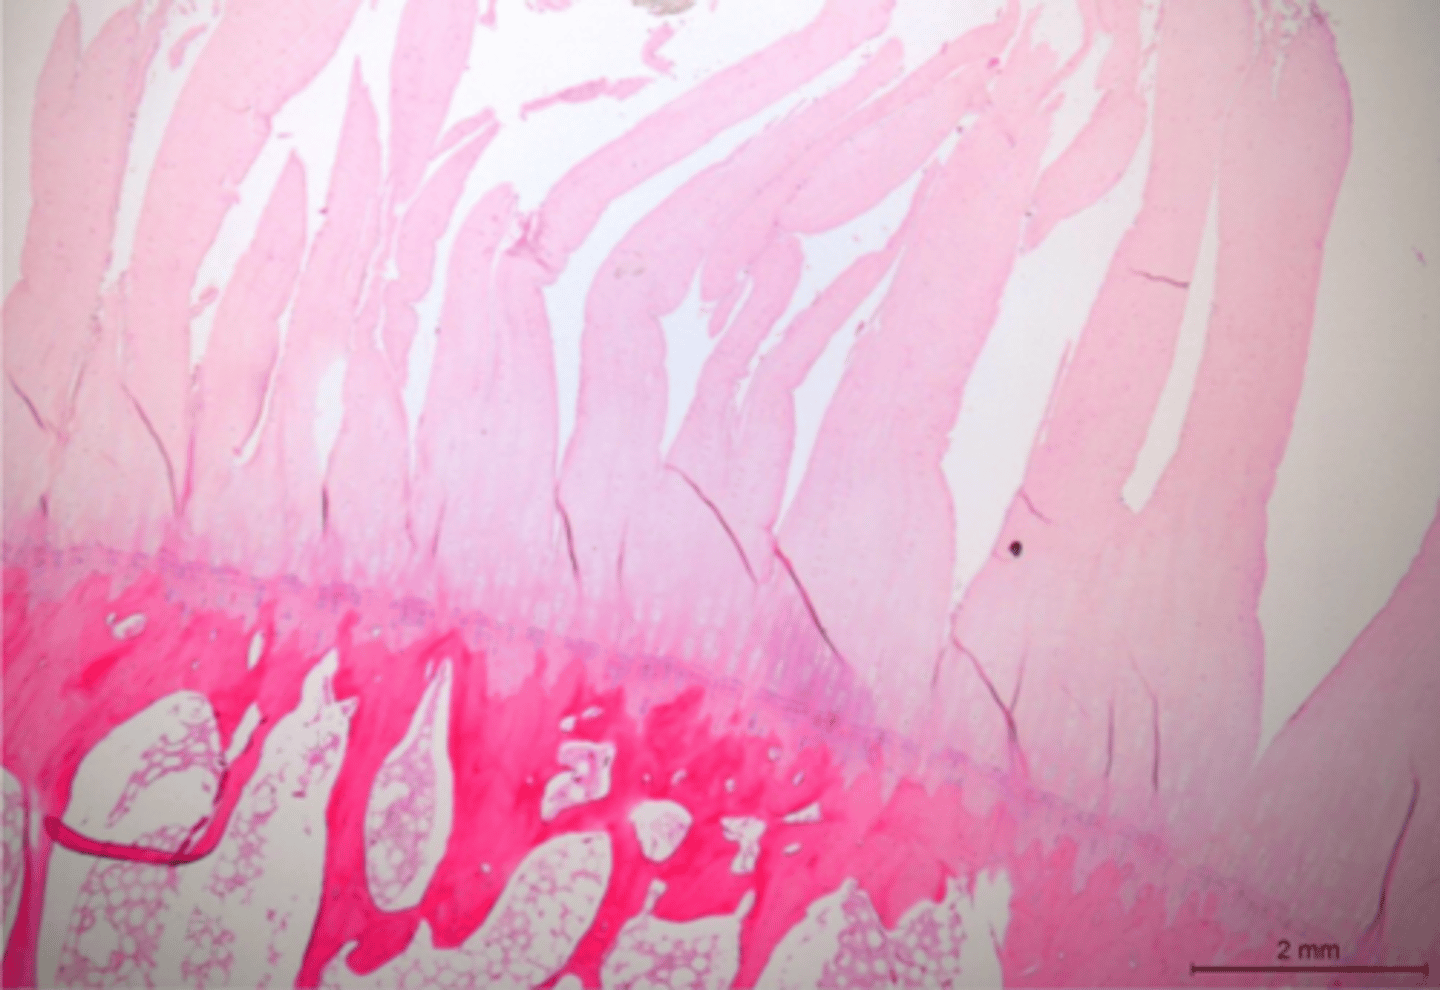

Identify the pathology:

Hypertrophic osteopathy